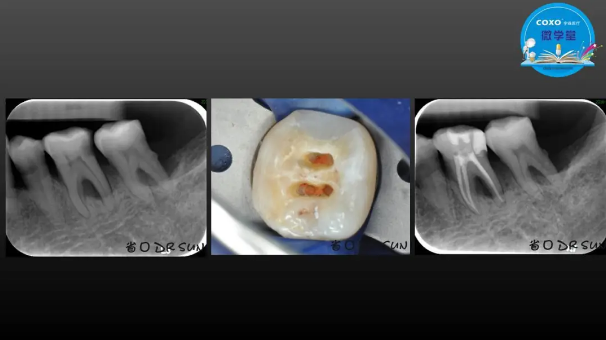

主任醫(yī)師,牙體牙髓副主任, 廣東省口腔醫(yī)院牙體牙髓科 主任醫(yī)師。2003年碩士研究生畢業(yè),研究方向?yàn)檠荔w牙髓病學(xué),擅長(zhǎng)于牙體牙髓病的診斷、齲齒、牙髓炎、根尖周病的治療以及前牙美容修復(fù)。